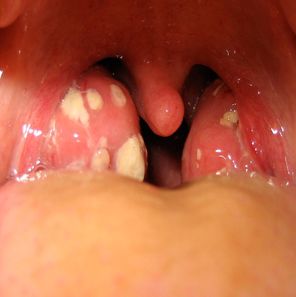

TRATAMIENTO DE FARINGITIS ESTREPTOCOCCICA EVALUACIÓN DE 3 TRATAMIENTOS DIFERENTES.

Los estudios prospectivos utilizando la erradicación bacteriana como el resultado final, han demostrado que una dosis diaria de amoxicilina, es tan efectiva como amoxicilina dos veces al día, para el tratamiento de faringitis estreptocócica  Grupo A β-hemolíticos  (GABHS).

La faringitis por GABHS es tratada para prevenir la fiebre reumática y para una discreta mejoría de los síntomas. Un tratamiento de 10 dias de amoxicilina (AMX) es lo recomendado habitualmente, en la práctica pedíatrica, dosificandose 2 o 3 veces por día.